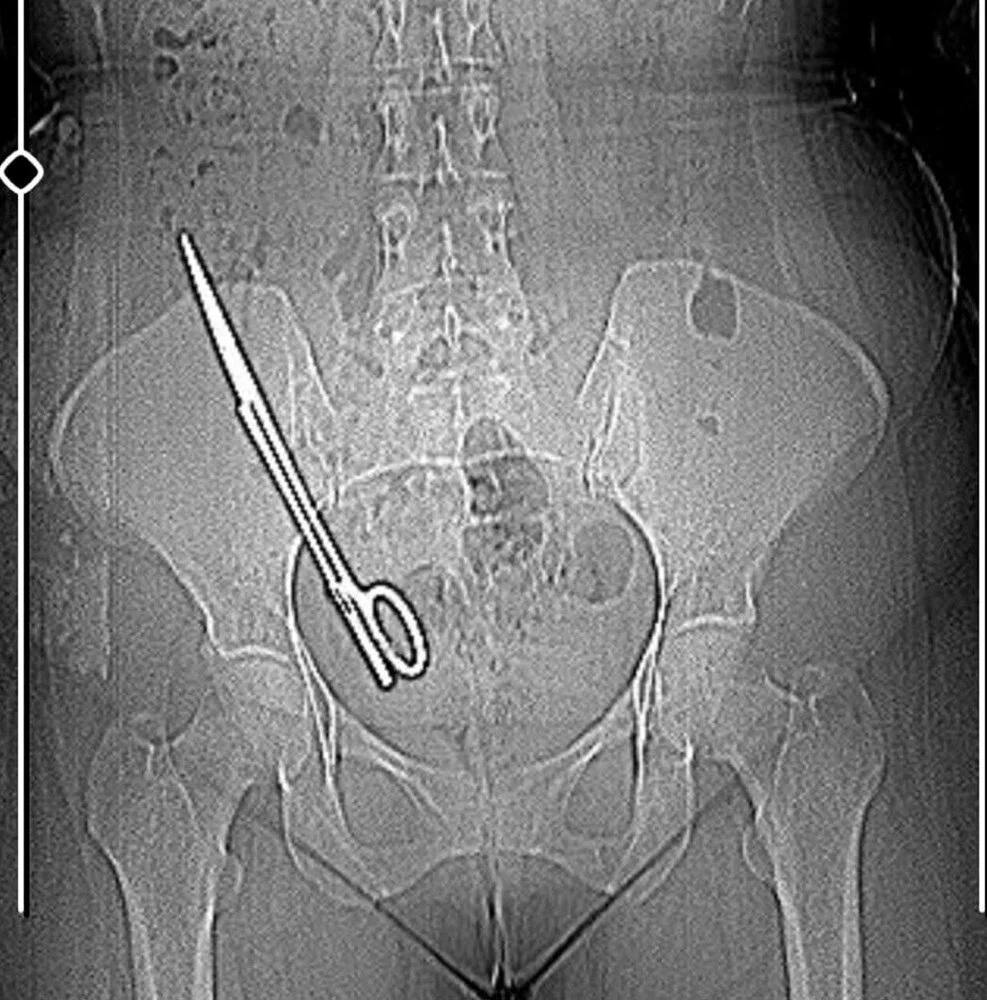

В Турции врачи обнаружили в животе 36-летней женщины хирургические ножницы, пролежавшие там 7 лет.

Женщина обратилась в больницу с жалобами на головную боль, которая началась после операции по удалению кисты в брюшной полости, проведённой в частной клинике. После обследования врачи нашли 16-сантиметровый инструмент, забытый хирургами. Ножницы удалили, а Фатма подала в суд на клинику.